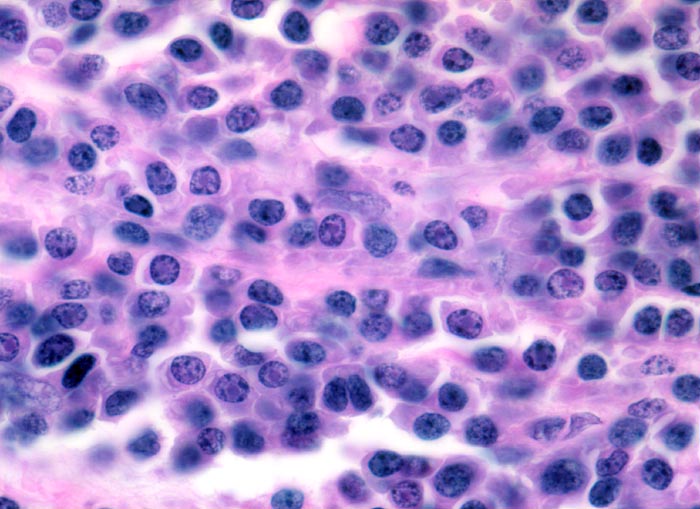

Morphologische Merkmale:

• Knochenmarkstanze mit nodulärer Hyperzellularität des blutbildenden Marks.

• In den hyperzellulären Arealen dichte Rasen neoplastischer atypischer Plasmazellen.

• In dieser Giemsa-Färbung sind die Plasmazellen gut erkennbar. Die Plasmazellen sind polymorph, vereinzelt mehrkernig. Exzentrisch im Zytoplasma lokalisierte vergrösserte Radspeichenkerne . Reichlich violettes Zytoplasma mit paranukleärer Aufhellung. Zellkerne teils mit vergrössertem Nukleolus.

• Ausserhalb der Plasmazellrasen findet sich spärlich residuelles blutbildendes Knochenmark.